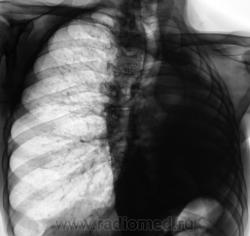

Пациент, заслуженный в прошлом, подданный "Его Величества", 10 лет тому был прооперирован - левосторонняя пульмонэктомия по поводу фиброзно-кавернозного туберкулёза. Вроде-бы все было нормально, время - от времени шел на встречу к работникам фтизиатрической службы, являясь после неоднократных напоминаний, делая им одолжение... Но в последние 3 года пропал. 2 месяца тому был найден, приглашен и явился. Чувствовал себя хорошо, даже не стал возражать против рентгенографии. Но смутили очаги, которых ранее не было в верхней доле правого лёгкого.

Повторили и "прямую", и произвели томограммы.

Очаговый туберкулез верхней доли?

А, не большая-ли площадь для очагового?

.....При гематогенном генезе подострого диссеминированого туберкулеза однотипная очаговая диссеминация локализуется в верхних и кортикальных отделах легких....

Так не миллиарный же, а просто - дисеминированый...если так посмотреть на вопрос?

Мы тоже склонились в пользу диссеминированного.

Важно то, что мы "посылальщика" упаковали. Выставлен диссеминированный туберкулёз.